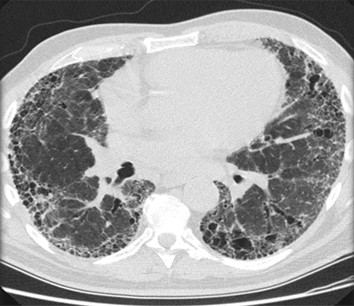

TC de alta resolução do tórax para procurar bronquiectasia (a qual nem sempre promove tosse produtiva), aspiração de corpo estranho, fibrose pulmonar ou outra doença pulmonar estrutural (que pode não aparecer bem na radiografia torácica). A doença pulmonar supurativa crônica é diagnosticada nos pacientes com sintomas clínicos de bronquiectasia, mas sem evidência radiográfica de bronquiectasia.[50] A TC também pode indicar a presença de um aneurisma aórtico ou um divertículo de Zenker. A expectativa quanto ao rendimento diagnóstico da TC do tórax em um paciente com tosse crônica e radiografia torácica normal é de que seja baixo.[3][Evidência C] Não há evidências de alta qualidade para apoiar o uso da TC de tórax na avaliação inicial dos pacientes com tosse crônica.[38]

[Figure caption and citation for the preceding image starts]: Tomografia computadorizada (TC) do tórax com presença de anel de sinete à esquerda em paciente com bronquiectasiaDo acervo pessoal da Dra. S.M. Bhorade, University of Chicago Medical Center [Citation ends].

[Figure caption and citation for the preceding image starts]: Tomografia computadorizada (TC) do tórax com vias aéreas dilatadas e espessadas e um padrão de árvore em brotamento periférico em paciente com bronquiectasiaDo acervo pessoal da Dra. S.M. Bhorade, University of Chicago Medical Center; usado com permissão [Citation ends].